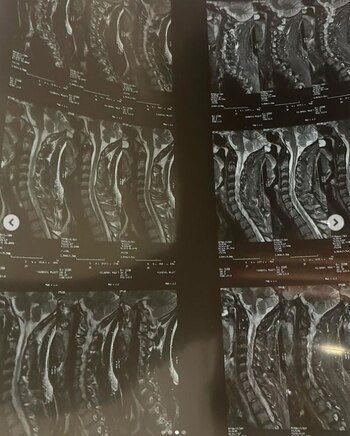

Un traumatólogo examinó la resonancia magnética de Figueroa, que ella misma había compartido en sus redes sociales, y desacreditó la afirmación de una grave lesión. Ángel de Brito, conductor del programa argentino LAM, difundió el análisis de Bruno Spinassi, un médico experto en lesiones lumbares.

De acuerdo con Spinassi, los discos de Figueroa solamente presentan deshidratación, algo común, y que no impide el ejercicio físico ni la participación en el baile.

El presentador de LAM, De Brito, cuestionó la veracidad de los datos aportados por Figueroa y el médico del ‘Bailando’, Norberto Furman, tras la evaluación de la imagen médica divulgada. “Ella subió una placa porque había mucha desconfianza, desconfiaban de la lesión de Milett en redes y como es la novia de Marcelo... y se la mandamos a analizar a un traumatólogo, para que nos diga cuál es la lesión que tiene”, comentó el presentador.

“Respondiendo en la pregunta si Milett podría seguir bailando basándome exclusivamente en las imágenes que ella subió la verdad es que no veo ningún impedimento, porque tener deshidratación de disco no justifica no hacer actividad física (...) en mi opinión, lo que haría sería evaluar su sistema postural, yo podría saber cuál es la causa de su problema, de sus dolores cervicales, porque la mayoría de las veces esos dolores no tienen que ver con problemas de los discos, sino con problemas musculares y posturales”, agregó el especialista.

De Brito manifestó su escepticismo hacia la versión de Figueroa diciendo: “No le cree nada en resumidas cuentas, por lo que muestra en esa placa que subió, quizás se guardó otras imágenes”. Esta situación deja abierta la controversia sobre el motivo real detrás de la rápida eliminación de Milett Figueroa del concurso de baile.